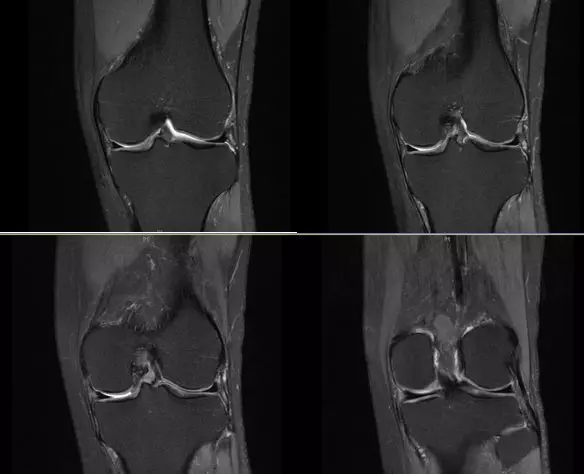

关节扭伤常常导致膝关节相关韧带结构的损伤,如何及时发现这些损伤并进行相关的治疗,是我们临床医师常常面临的问题,除了相关病史、临床体征之外,磁共振扫描也是重要的诊断依据

膝关节的解剖结构

正常的膝关节

韧带结构:形态,张力,质地,连续性

半月板:完整性,形态,质地